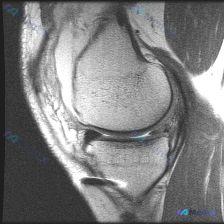

这是一张膝关节矢状位T2加权MRI,观察层面为膝关节外侧室,可显示股骨外侧髁、胫骨外侧平台、外侧半月板体部结构。

- 半月板:外侧半月板体部轮廓保留,但内部可见线状高信号影,且信号明确延伸至关节面,这是本例最关键的阳性发现。

结合现有影像信息,最符合的诊断是外侧半月板体部撕裂。根据信号形态,优先考虑垂直型创伤性撕裂或退变性水平撕裂;没有关节积液和骨髓水肿,提示要么是慢性撕裂,要么是低能量损伤导致的撕裂,退变可能是并存的基础改变。